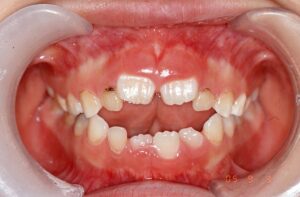

〈1〉

初診時の口腔内の写真です。

開咬で舌癖もあったので、口腔機能療法(MFT)をしていただきました。

口腔機能療法(MFT)だけでここまで綺麗な歯列にすることができました。